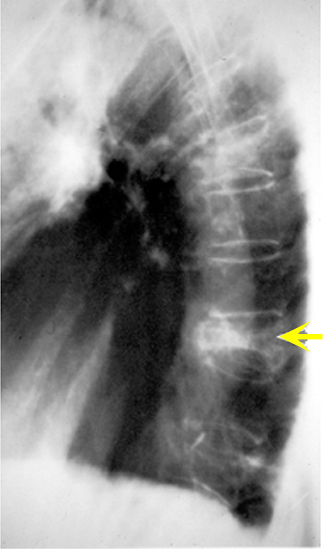

Figure 1: X-ray of the thoracic spine (lateral view)

Compression fracture / Osteoporosis

Case 1:

82 year old thin female with back pain for several months. Her back pain began after a minor fall that she had several months ago.

Imaging findings: Figure 1

Compression fracture of the thoracic spine (arrow) due to osteoporosis.

Osteoporotic fracture is commonly wedge shaped and on x-ray the vertebral body is of decreased density. The compression fracture can be traumatic or due to osteoporosis. In compression fracture the vertebral body is biconcave in shape due to central end-plate collapse.